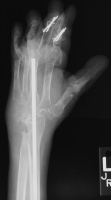

Below are xrays after the first set of reconstructions.

Highslide

For the second stage of her reconstruction, the index proximal phalanx did not have adequate dorsal cortex to support an implant arthroplasty, and bone graft from the metacarpal head was used to reconstruct this.